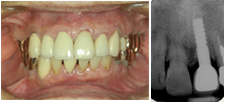

もし自分が酔っぱらって転倒し、上顎前歯を1本折って欠損になったとしたら、絶対にブリッジではなく、1ピースAQBを1本植立してもらい、メタルボンド冠で直そうと思う。

植立後約19年の症例を筆頭に多数のAQB長期経過症例のメインテナンスを日頃担当している筆者の診療所のスタッフも恐らく同じ選択をするであろう。

それ程欠損補綴で信頼に足るすばらしい治療法として臨床的に実証されているので、やはり広く国民にその恩恵を提供したいと思うわけである。